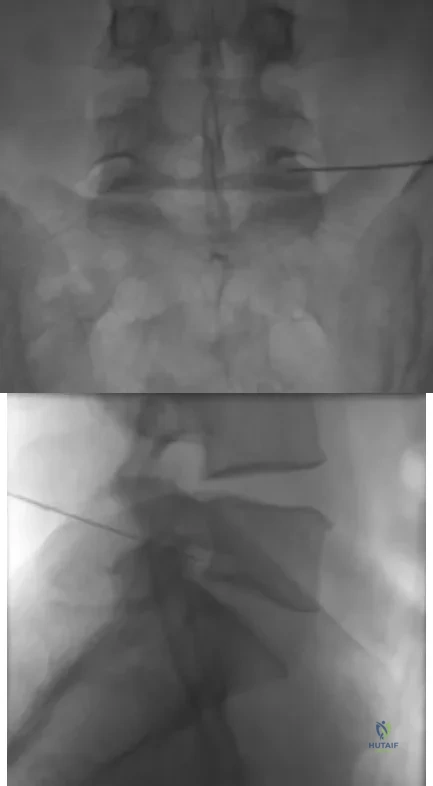

The injection shown in Figures 1a and 1b would most benefit a patient who reports which of the following symptoms?

Explanation